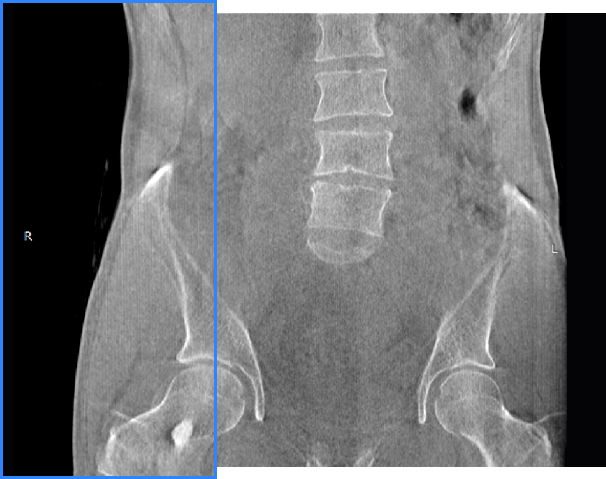

髖關節